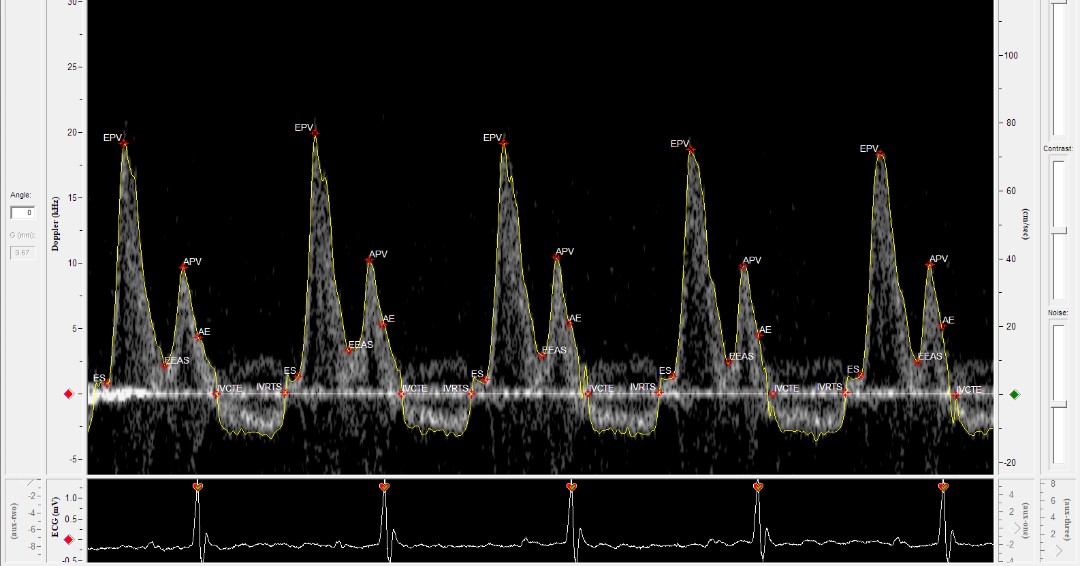

@RushUniversity is studying#diastolic#dysfunction in#ageing and#pregnancy#mice with the#DFVS from@IndusInstrument. Check out this#mitralsignal acquired with the#Doppler Flow Velocity System.#CardiovascularResearch#PreClinical#DopplerUltrasound#LearnMorepic.twitter.com/zG4Puqddxx